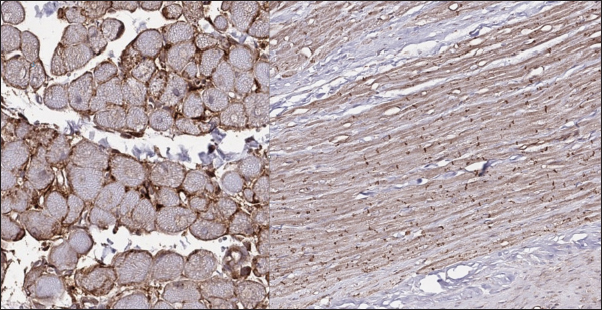

In the myocardial samples of the cats with RCM, we found zones of slightly dystrophic cardiomyocytes surrounded by areas of diffuse or patchy fibroses, and some loci had compact fibrosis associated with subendocardial spaces. Slides stained with Masson’s trichrome showed areas of significant interstitial, compact subendocardial fibrosis (Fig. 8). Immunohistochemical staining with anti-Cx43 antibodies showed the partial absence of Cx-43 positive staining despite the presence of fibrotic tissue (Fig. 9). Additionally, some loci showed increased lateral expression of the Cx43 proteins. In certain longitudinal slides, we observed intermittent patterns in the stained structures of intercalated disks. In some cardiomyocytes, Cx43 immunostaining revealed granular structures within intercalated discs and the cytoplasm (Fig. 10).

Fig. 9. Immunohistochemistry. RCM group. Longitudinal section, Cx43 proteins found in zones of cell-to-cell contact and laterally, but could be stochastically reduced in other cells. Stained with Cx43 antibodies.

Fig. 10. Immunohistochemistry. RCM group. Longitudinal section, Cx43 proteins found in zones of cell-tocell contact but do not form solid bands in contact zones, while presented in intermittent pattern or as granules on the cell’s pole/ in cytoplasm. Stained with Cx43 antibodies.